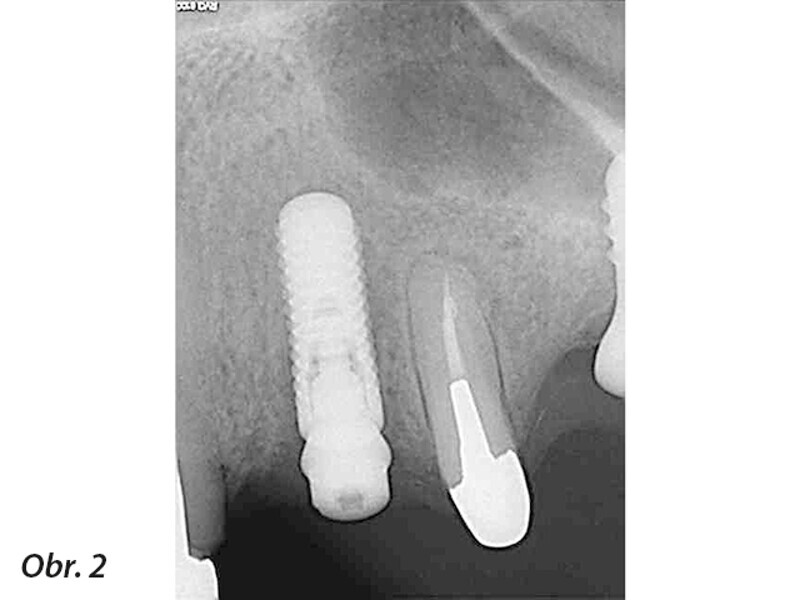

Periapikální léze implantátů a retrográdní periimplantitis – dva stavy nepříliš zdokumentované